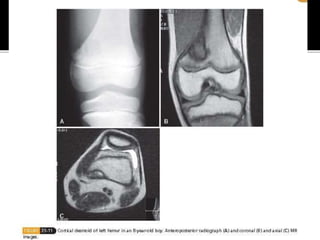

 Irregularity in the posteromedial aspect of

the distal femoral epiphysis, possibly a

reaction to the pull of adductor magnus

 2nd decade of life. Males.

 Usually asymptomatic. Xray shows erosion of

the posteromedial distal femoral cortex with

a sclerotic base. Best seen with LL externally

rotated 20-45 degrees.

 Histology – Fibrous tissue with collagenous

stroma. Similar to NOF.

 Treatment - Observation